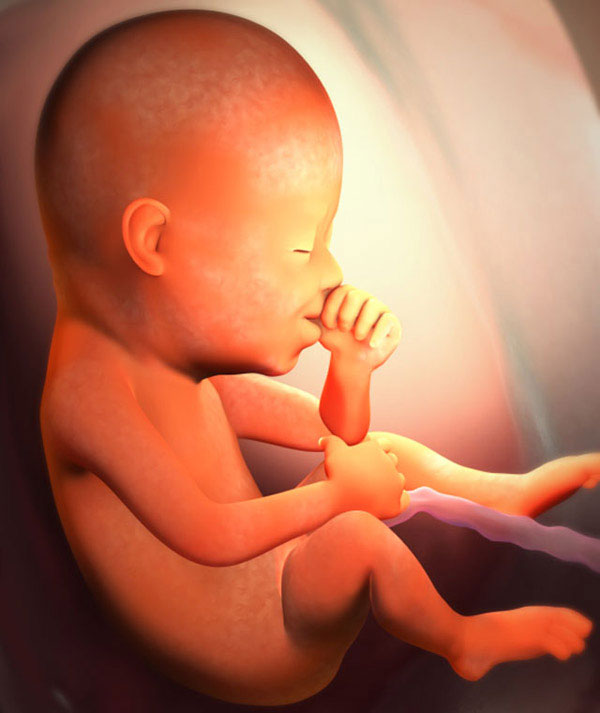

Agora, a principal tarefa do feto é crescer e ganhar peso. O garoto parece um homenzinho. Em proporções do corpo, ele já se assemelha a um recém-nascido. Se seu bebê está destinado a nascer com pêlos na cabeça, então nessa época eles aparecem. Pequenas sobrancelhas e cílios já estão lá, mas é mais provável que não sejam pêlos, mas um cotão leve. Seu filho está constantemente treinando. Pelos sinais do cérebro, o feto literalmente realiza os movimentos de que precisará primeiro.

Nesta semana, a fruta crescerá 18 cm e seu peso atingirá cerca de trezentos gramas. Não se esqueça: seu bebê já ouve, então fale com ele.

O que há de novo para o bebê? A melhoria da composição do sangue continua. Os corpos vermelhos são formados há muito tempo e os brancos estão em processo. Mais tarde, juntamente com outros sistemas, serão responsáveis pela imunidade da criança. E em uma linguagem minúscula, as papilas gustativas continuam a se formar. Quando um líquido amniótico entra na boca do feto, ele já é capaz de distinguir seu sabor.